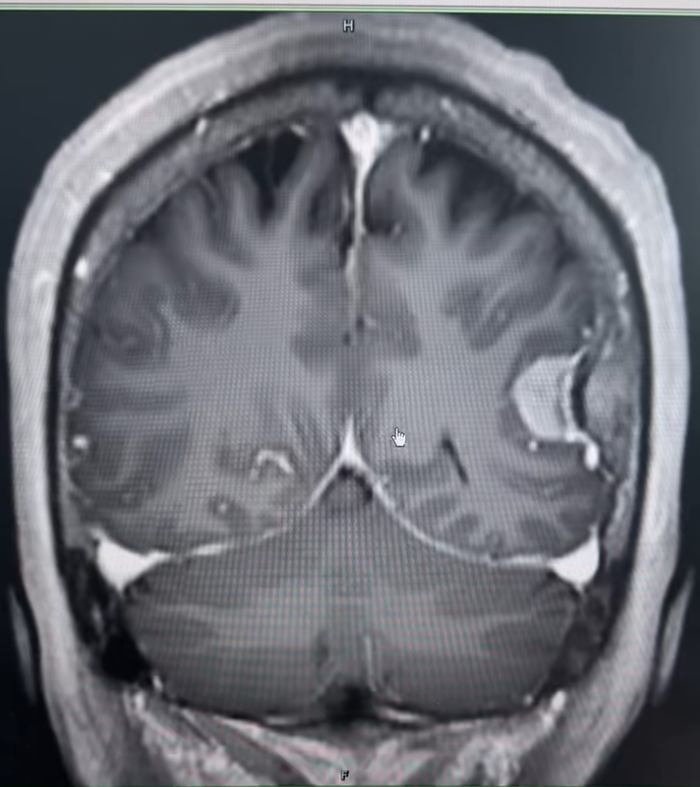

在青海大学附属医院,另一例颅内肿瘤手术同样面临挑战。该患者术前影像考虑脑膜瘤,尽管肿瘤体积不大,但肿瘤位置特殊——位于左侧顶叶,运动区附近,血运丰富,患者术前肢体已有症状,一旦损伤可造成严重的并发症。王虎主任与当地专家术前经过充分的讨论与准备,制定了完善的手术方案。

术中,王虎主任最终仅用时2小时就将肿瘤全部切除,并且术后未造成任何并发症,不仅解决了患者的难题,也促进了两院的合作。